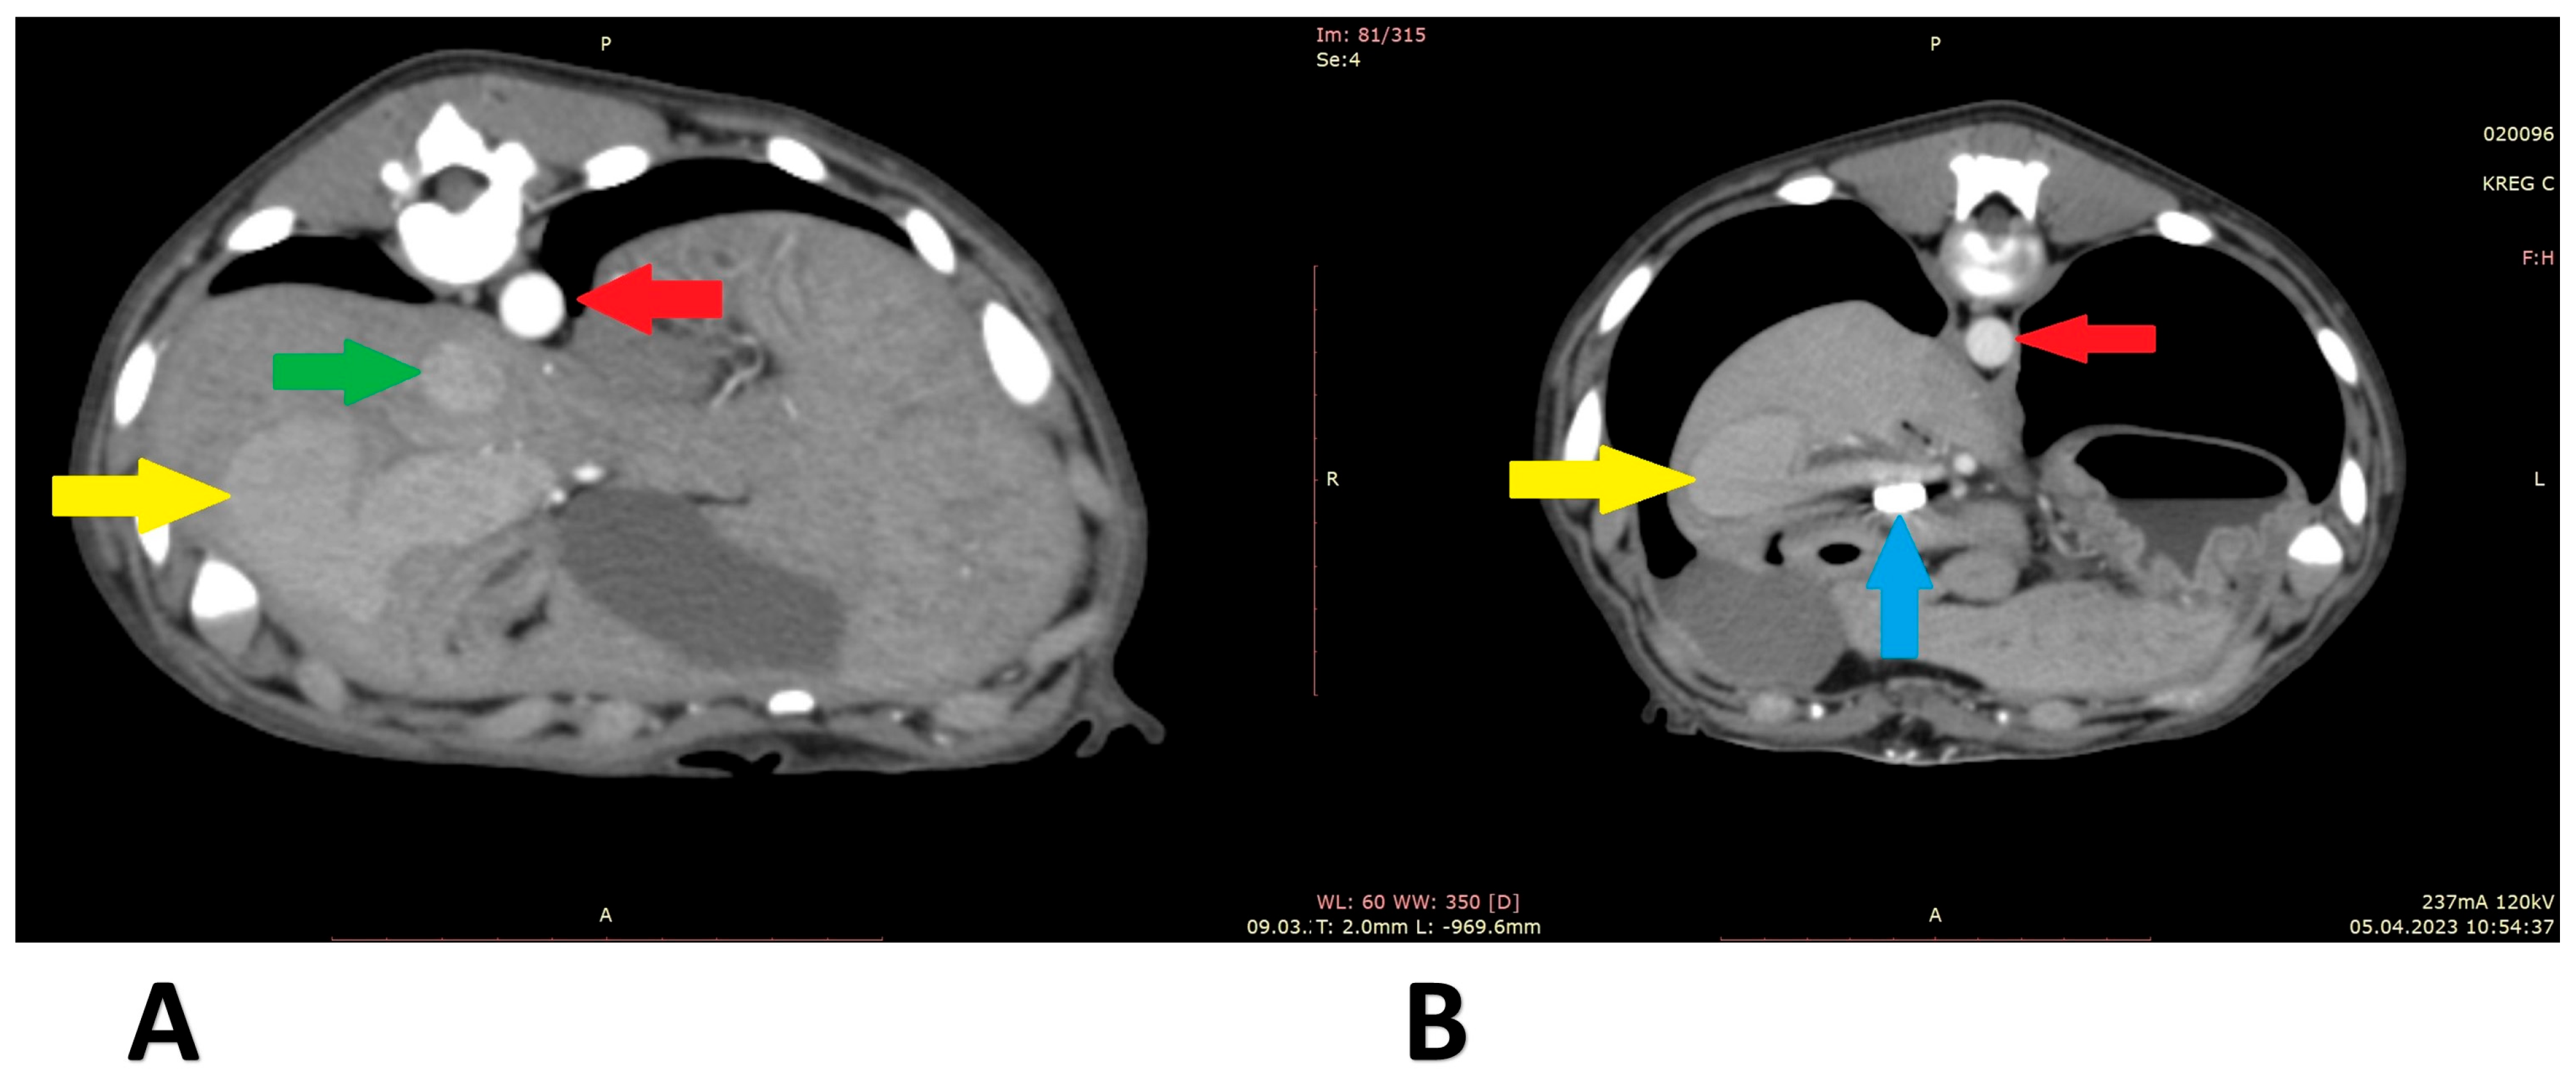

3.1. Case 1

3.2. Case 2

3.3. Case 3

3.4. Case 4